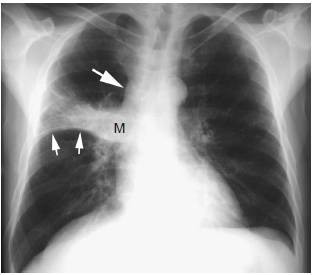

鳞状细胞癌伴支气管阻塞和肺不张

中央型肺癌的横s或者反s征,是指右侧中央型肺癌的正位x光胸片上的典型

侧位胸片显示左下叶局部肺不张及实变,肺门内有气体